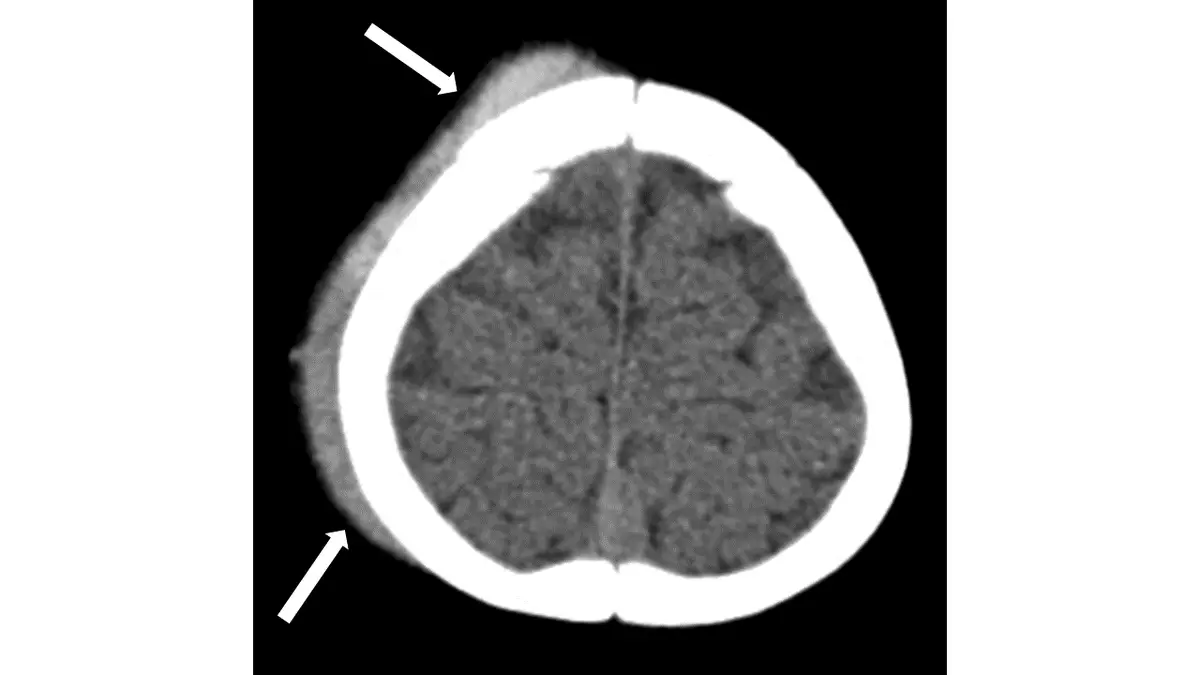

頭部外傷病人電腦斷層攝影呈現如下圖,下列有關箭號的敘述何者最正確?

本題影像為頭部外傷後的非增強電腦斷層(NECT)橫斷面,可見:

- 白色箭號(兩個)所指位置:位於左側頭部顱骨(calvarium/skull)外側,可見明顯高密度(白色/亮白)的局部軟組織腫塊。此高密度區域位於顱骨外板(outer table)之外,在頭皮軟組織層內,屬於顱骨外的結構。

- 顱骨:顯示為高密度骨性結構(白色),兩側對稱,未見明顯骨折線(但需仔細評估)。

- 顱內:腦實質密度均勻,大腦鐮(falx)可見,未見明顯顱內高密度血腫(無透鏡形或新月形顱內血腫)。

- 左側頭皮層:可見與顱骨外板緊貼的高密度腫塊,形狀較局限,位於頭皮之中,為急性血液的高密度表現(CT 值約 40–60 HU)。

關鍵判斷:箭號所指的高密度結構完全位於顱骨外側(顱外),而非在顱骨與硬腦膜之間(硬腦膜上血腫),也非在硬腦膜下腔(硬腦膜下血腫),更非在蜘蛛網膜下腔。此為頭皮下血腫的典型表現。